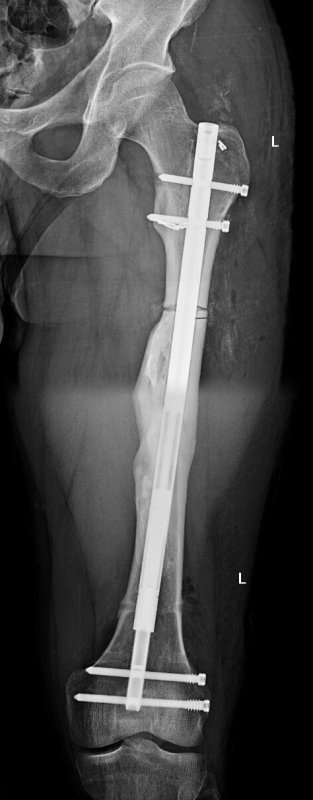

Bravurní výkon provedli lékaři z Kliniky úrazové chirurgie Fakultní nemocnice Brno. Pacientovi, který měl po úraze tříštivou zlomeninu stehenní kosti, čímž došlo k jejímu zkrácení o 3,5 cm, nyní provedli operační zákrok, který povede k prodloužení kosti tak, aby nekulhal a mohl se běžně pohybovat.

V rámci Fakultní nemocnice Brno se jedná o raritní operaci a jednu z mála, která se provádí v České republice. Hlavním operatérem byl vedoucí lékař Kliniky úrazové chirurgie a zástupce přednosty pro školství MUDr. Milan Krtička, Ph.D.